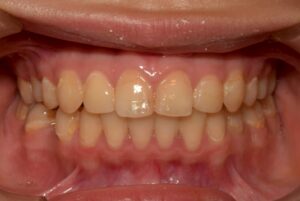

19歳 の お嬢さん です。

兵庫県川西市 畑矯正歯科 にて

歯科矯正治療が 終了 しました。

クアラルンプール生活 が 長かった 彼女。

このまま では 【虫歯だらけ】 に!

彼女

美人 なん です。